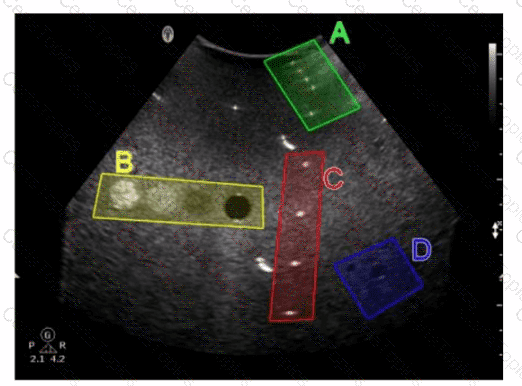

Which target group in this image of a tissue-mimicking phantom is used for gray-scale evaluation?

Options:

A.

Option A

B.

Option B

C.

Option C

D.

Option D